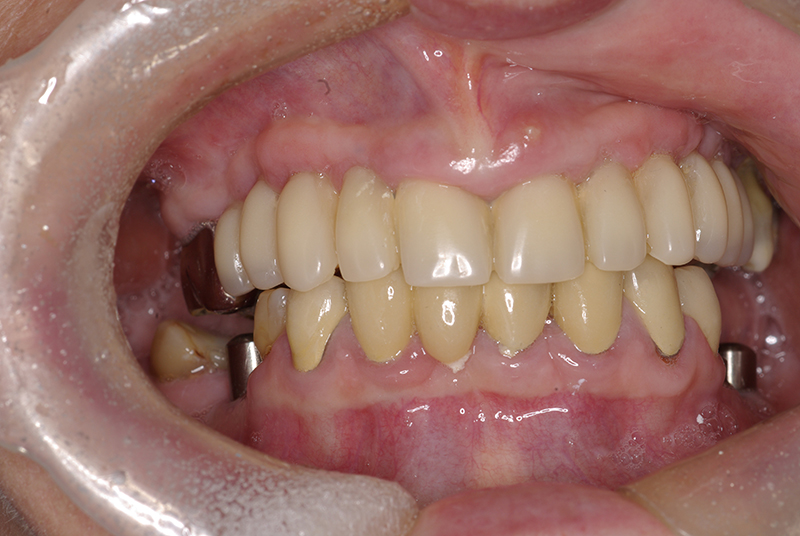

Na Clínica Pontes Odontologia, somos referência em implantes dentários em Fortaleza, oferecendo tratamentos de alta qualidade e tecnologia de ponta. Os implantes dentários são estruturas de titânio posicionadas cirurgicamente no osso maxilar ou mandibular para substituir as raízes dos dentes ausentes. Essa técnica permite a fixação de próteses personalizadas, restaurando a função mastigatória, a estética e a autoestima dos nossos pacientes.